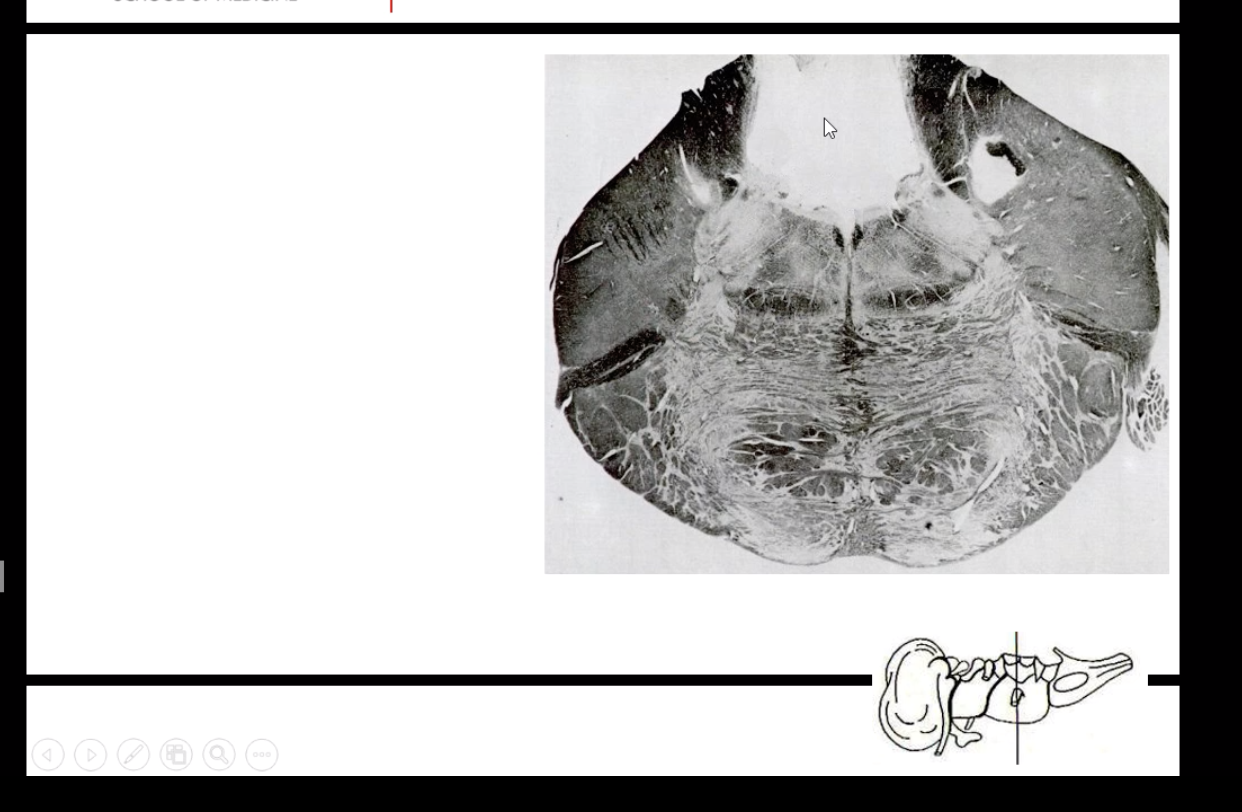

What spinal cord level is this?

What are the feautures of it?

Why does lumbar have less white matter than grey matter?

All the corticospinal axons from upper body have peeled off by then. Also just starting to bring in sensory information, so very few fibers. As you get higher you will get more white matter